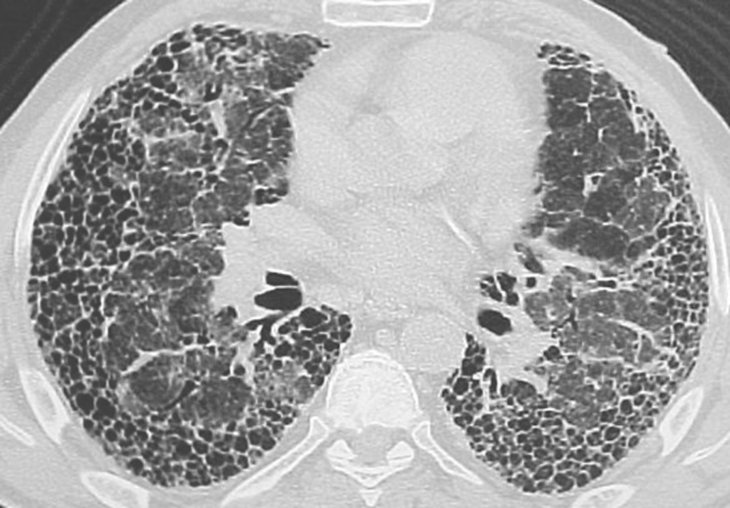

Way back in January 2019, Musi and his colleagues published a study on EBioMedicine journal on the results of a drug trial they conducted on 14 human patients. These patients suffer from Idiopathic Pulmonary Fibrosis (IPF), which is fatal by nature. Their only saving grace being a concoction of drugs that the researchers believed would eliminate senescent cells in their body. The drugs did not just ‘rejuvenate’ them in the literal sense; they were also especially useful at improving their state of health.